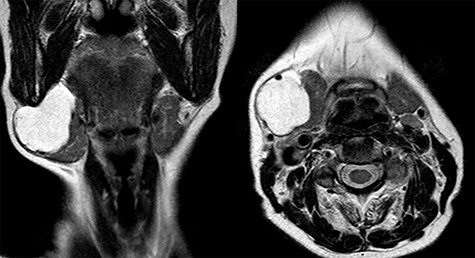

Magnetic resonance imaging (MRI) was performed and showed a cystic mass of 4 × 4 × 3.5 cm in size located under the right mandible and strictly adherent to the submandibular gland. On T2-weighted images, the mass resulted hyperintense, while hypointense in those T1 weighted (Fig. 2).

Assessment methods include US, CT scan and MRI. US examination should be performed as first imaging approach and it usually shows an anechoic multilobulated cystic mass. A CT scan or better a MRI may be performed in order to do a most accurate presurgery evaluation. On MRI, T1-weighted images show an isointense signal and T2-weighted images show a hyperintense signal without contrast enhancement.